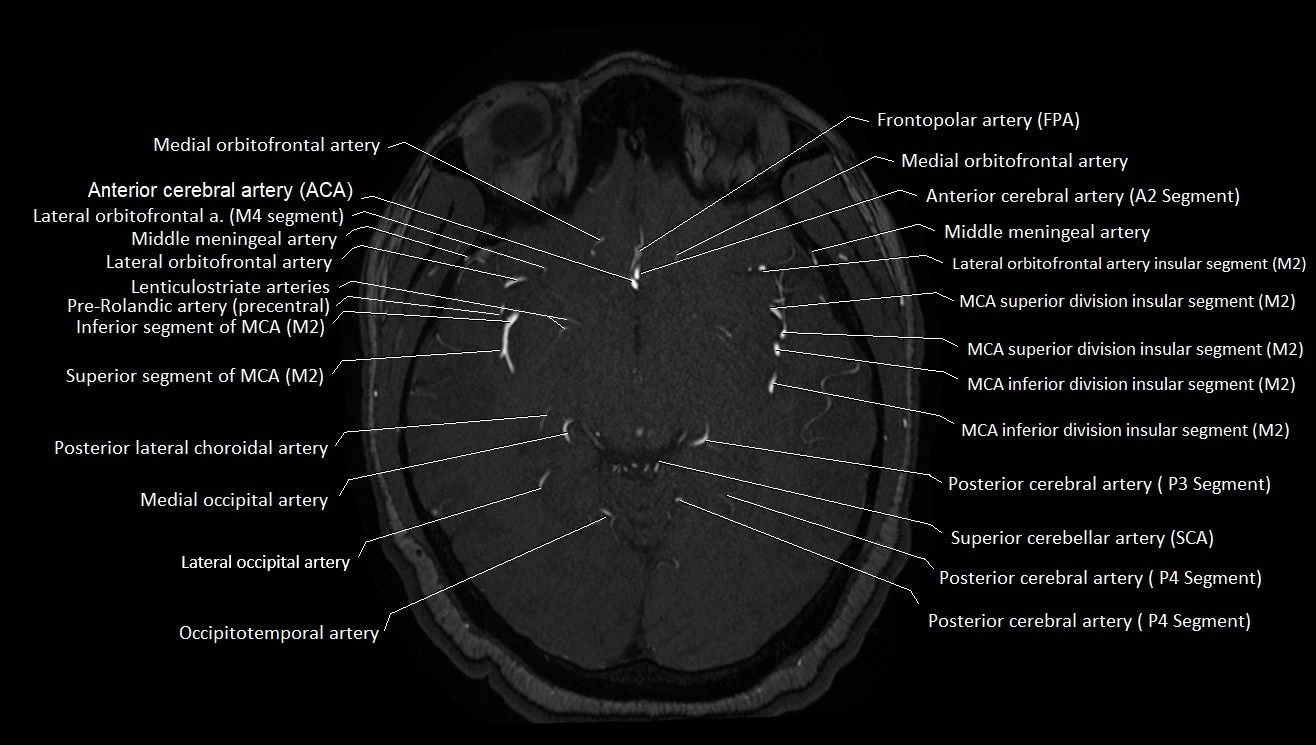

MRI images

image